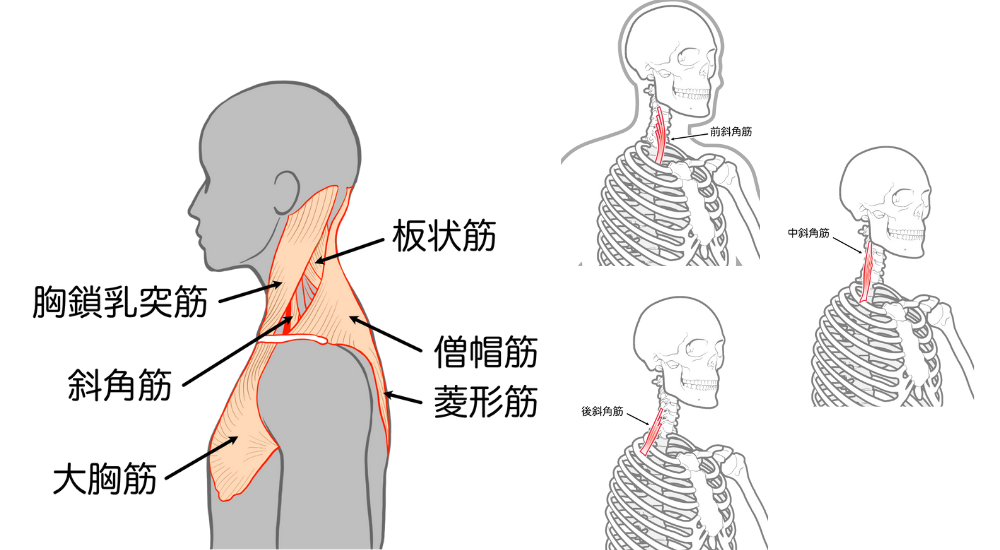

- 斜角筋: 首の側面。ストレートネックや巻き肩で硬くなりやすく、神経や血管の圧迫(胸郭出口症候群)による腕の痺れに関与します。